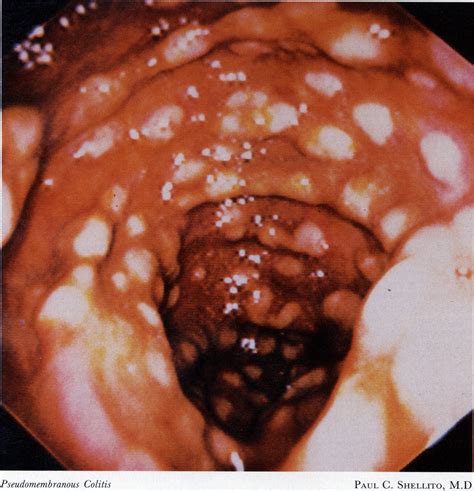

Alright guys, let’s start with the basics. Pseudomembranous colitis , often shortened to PMC, is a type of inflammation of the large intestine (your colon) that’s typically caused by an overgrowth of a nasty bacteria called Clostridioides difficile , or C. diff for short. Now, C. diff is a bacteria that can live in your gut without causing problems for many people. But, when something disrupts the natural balance of bacteria in your colon – often due to antibiotic use – C. diff can multiply like crazy. As it grows, it releases toxins that damage the lining of your colon, leading to inflammation and the formation of those characteristic yellowish-white plaques, or “pseudomembranes,” on the colon’s surface. These aren’t actual membranes, but rather a buildup of inflammatory cells, dead tissue, and fibrin. It’s this buildup that gives the condition its name and can cause some seriously uncomfortable symptoms. Understanding the root cause , which is often antibiotic-associated, is the first step in grasping how PMC develops and how we can combat it. It’s a classic example of how our gut microbiome, that delicate ecosystem of bacteria living inside us, is crucial for our health. When that balance is thrown off, even by something as common as antibiotics meant to fight other infections, we can face unexpected and serious health issues like PMC. The severity can range from mild diarrhea to life-threatening conditions, so it’s definitely something we need to pay attention to.

Often, labs will use a combination of these tests to ensure accuracy. Sometimes, if the diagnosis is unclear or if there are signs of complications, a colonoscopy or sigmoidoscopy might be performed. This involves inserting a flexible tube with a camera into the colon to visualize the inflammation and the characteristic pseudomembranes directly. Biopsies can also be taken during this procedure for further analysis. It’s a bit invasive, but it can provide clear visual evidence. Blood tests might also be done to check for signs of infection, dehydration, or electrolyte imbalances. The goal is to catch it early and confirm the diagnosis so that the right treatment can be started as quickly as possible. Modern diagnostic techniques are constantly improving, making it easier and faster to identify C. diff infections and ensure patients get the care they need. It’s a crucial part of the battle against this challenging condition.